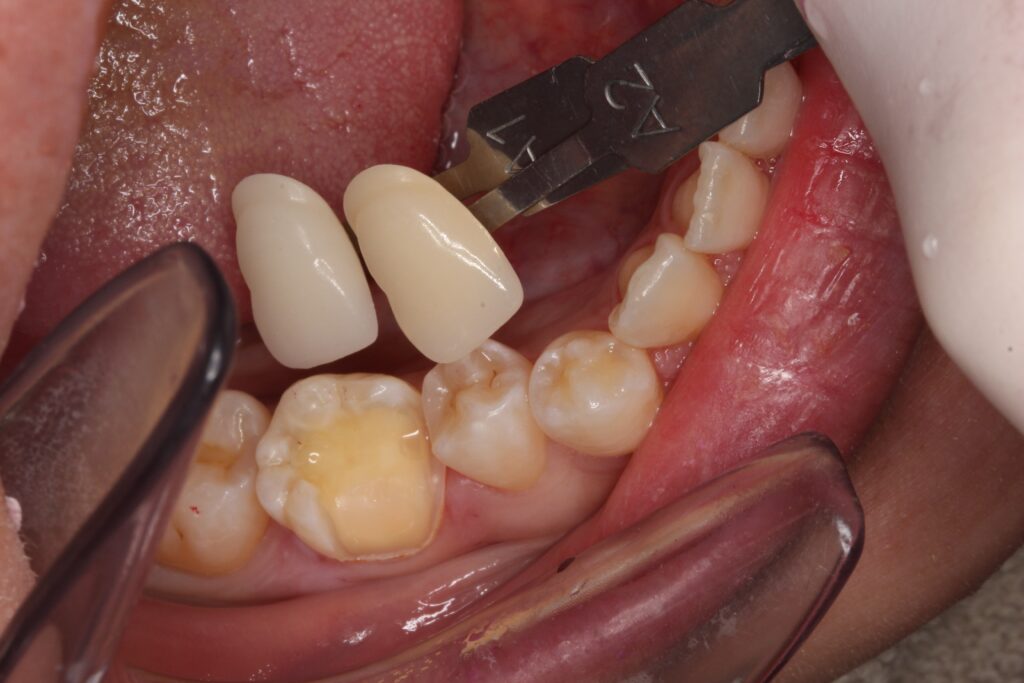

歯の色を合わせ、形を成形して、これで治療が終わります。

大きな虫歯は、表面をレジンでコーティングして、

セラミックが入るように形を整えています。

後は、型取りを行います。

歯の色を記録します。色見本を元に、その方に合った歯の色を確認します。

後日、出来上がったセラミックインレー(部分的な詰め物)をセットして、

治療を終えます。

セラミックがセットされt状態です。

綺麗にセラミックが入りました(^^)/

治療をした箇所が分かりますでしょうか。